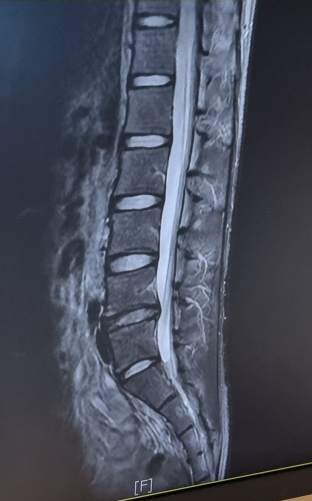

요추4-5번 추간판의 좌신경공 돌출 및 좌측 신경공 협착이라 하는데

해당 영상컷 자체는 심해보이지는 않습니다.

하지만 여러장을 보면서 확인을 해야 정확한 상태체크가 가능하겠습니다.

영상으로 보건대 심해 보이지 않습니다

해당 사진 한 장만 놓고 정확한 판단을 내릴 수는 없지만, 정도가 심하지 않아 보이며, 적절한 치료를 통해서 최대한 치료를 해볼 수 있을 것으로 사료됩니다. 혼자서 재활하는 것은 추천드리지 않으며 심하지 않더라도 병원에 다니면서 관리하시는 것을 추천드립니다.

이 사진만 봐서는 디스크탈출의 정도가 심하지 않습니다. 단면 사진도 같이 봐야 정확한 신경압박 및 디스크탈출 정도를 알 수 있습니다.

이 사진만 보고 가늠하자면 충분히 회복이 가능한 상태일 가능성이 높아보입니다.

요추4-5번 추간판의 좌신경공 돌출 및 좌측 신경공 협착이 저명히 관찰되고 있습니다.